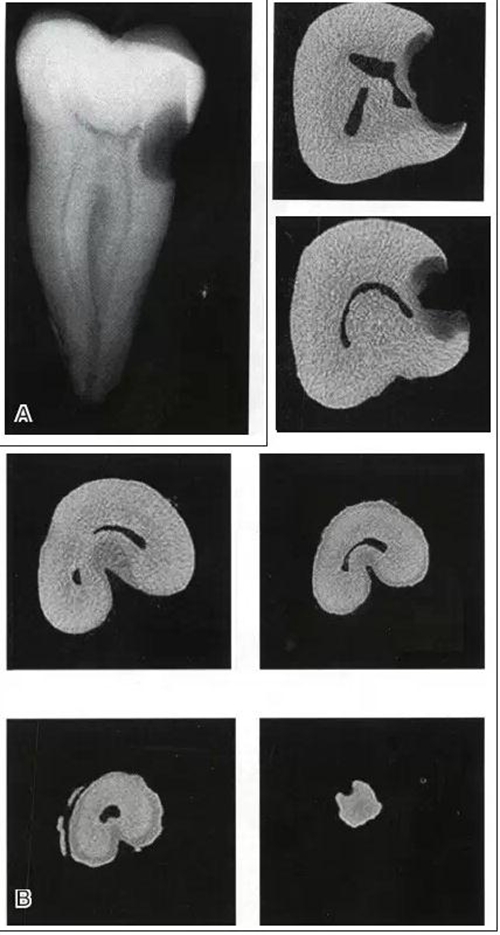

與傳統(tǒng)根管形態(tài)概念不同,C形根管形態(tài)從根管口到根尖有很大變異(圖1)。有些斷面呈C形,有些又呈分號(hào)形,有些斷面僅呈點(diǎn)狀。

圖1 下頜第二磨牙C形根管系統(tǒng)的形態(tài)從根管口到根尖(A~H)可發(fā)生巨大變化